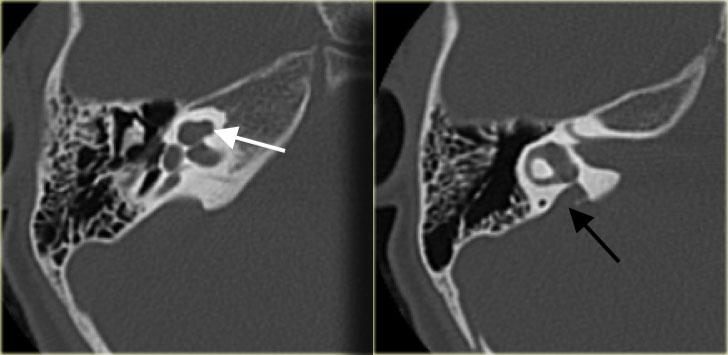

Cống tiền đình giãn rộng hai bên (mũi tên đen). Trụ ốc tai xương không quan sát thấy (mũi tên trắng).

Bên trái là hình ảnh của một bệnh nhân có cống tiền đình giãn rộng hai bên.

Lưu ý rằng trụ ốc tai xương không quan sát thấy.

Bên trái là hình ảnh của một bé trai 5 tuổi với tình trạng nghe kém tiến triển hai bên.

Quan sát thấy cống tiền đình giãn rộng (mũi tên đen).

Ốc tai không có trụ ốc tai xương (mũi tên trắng).